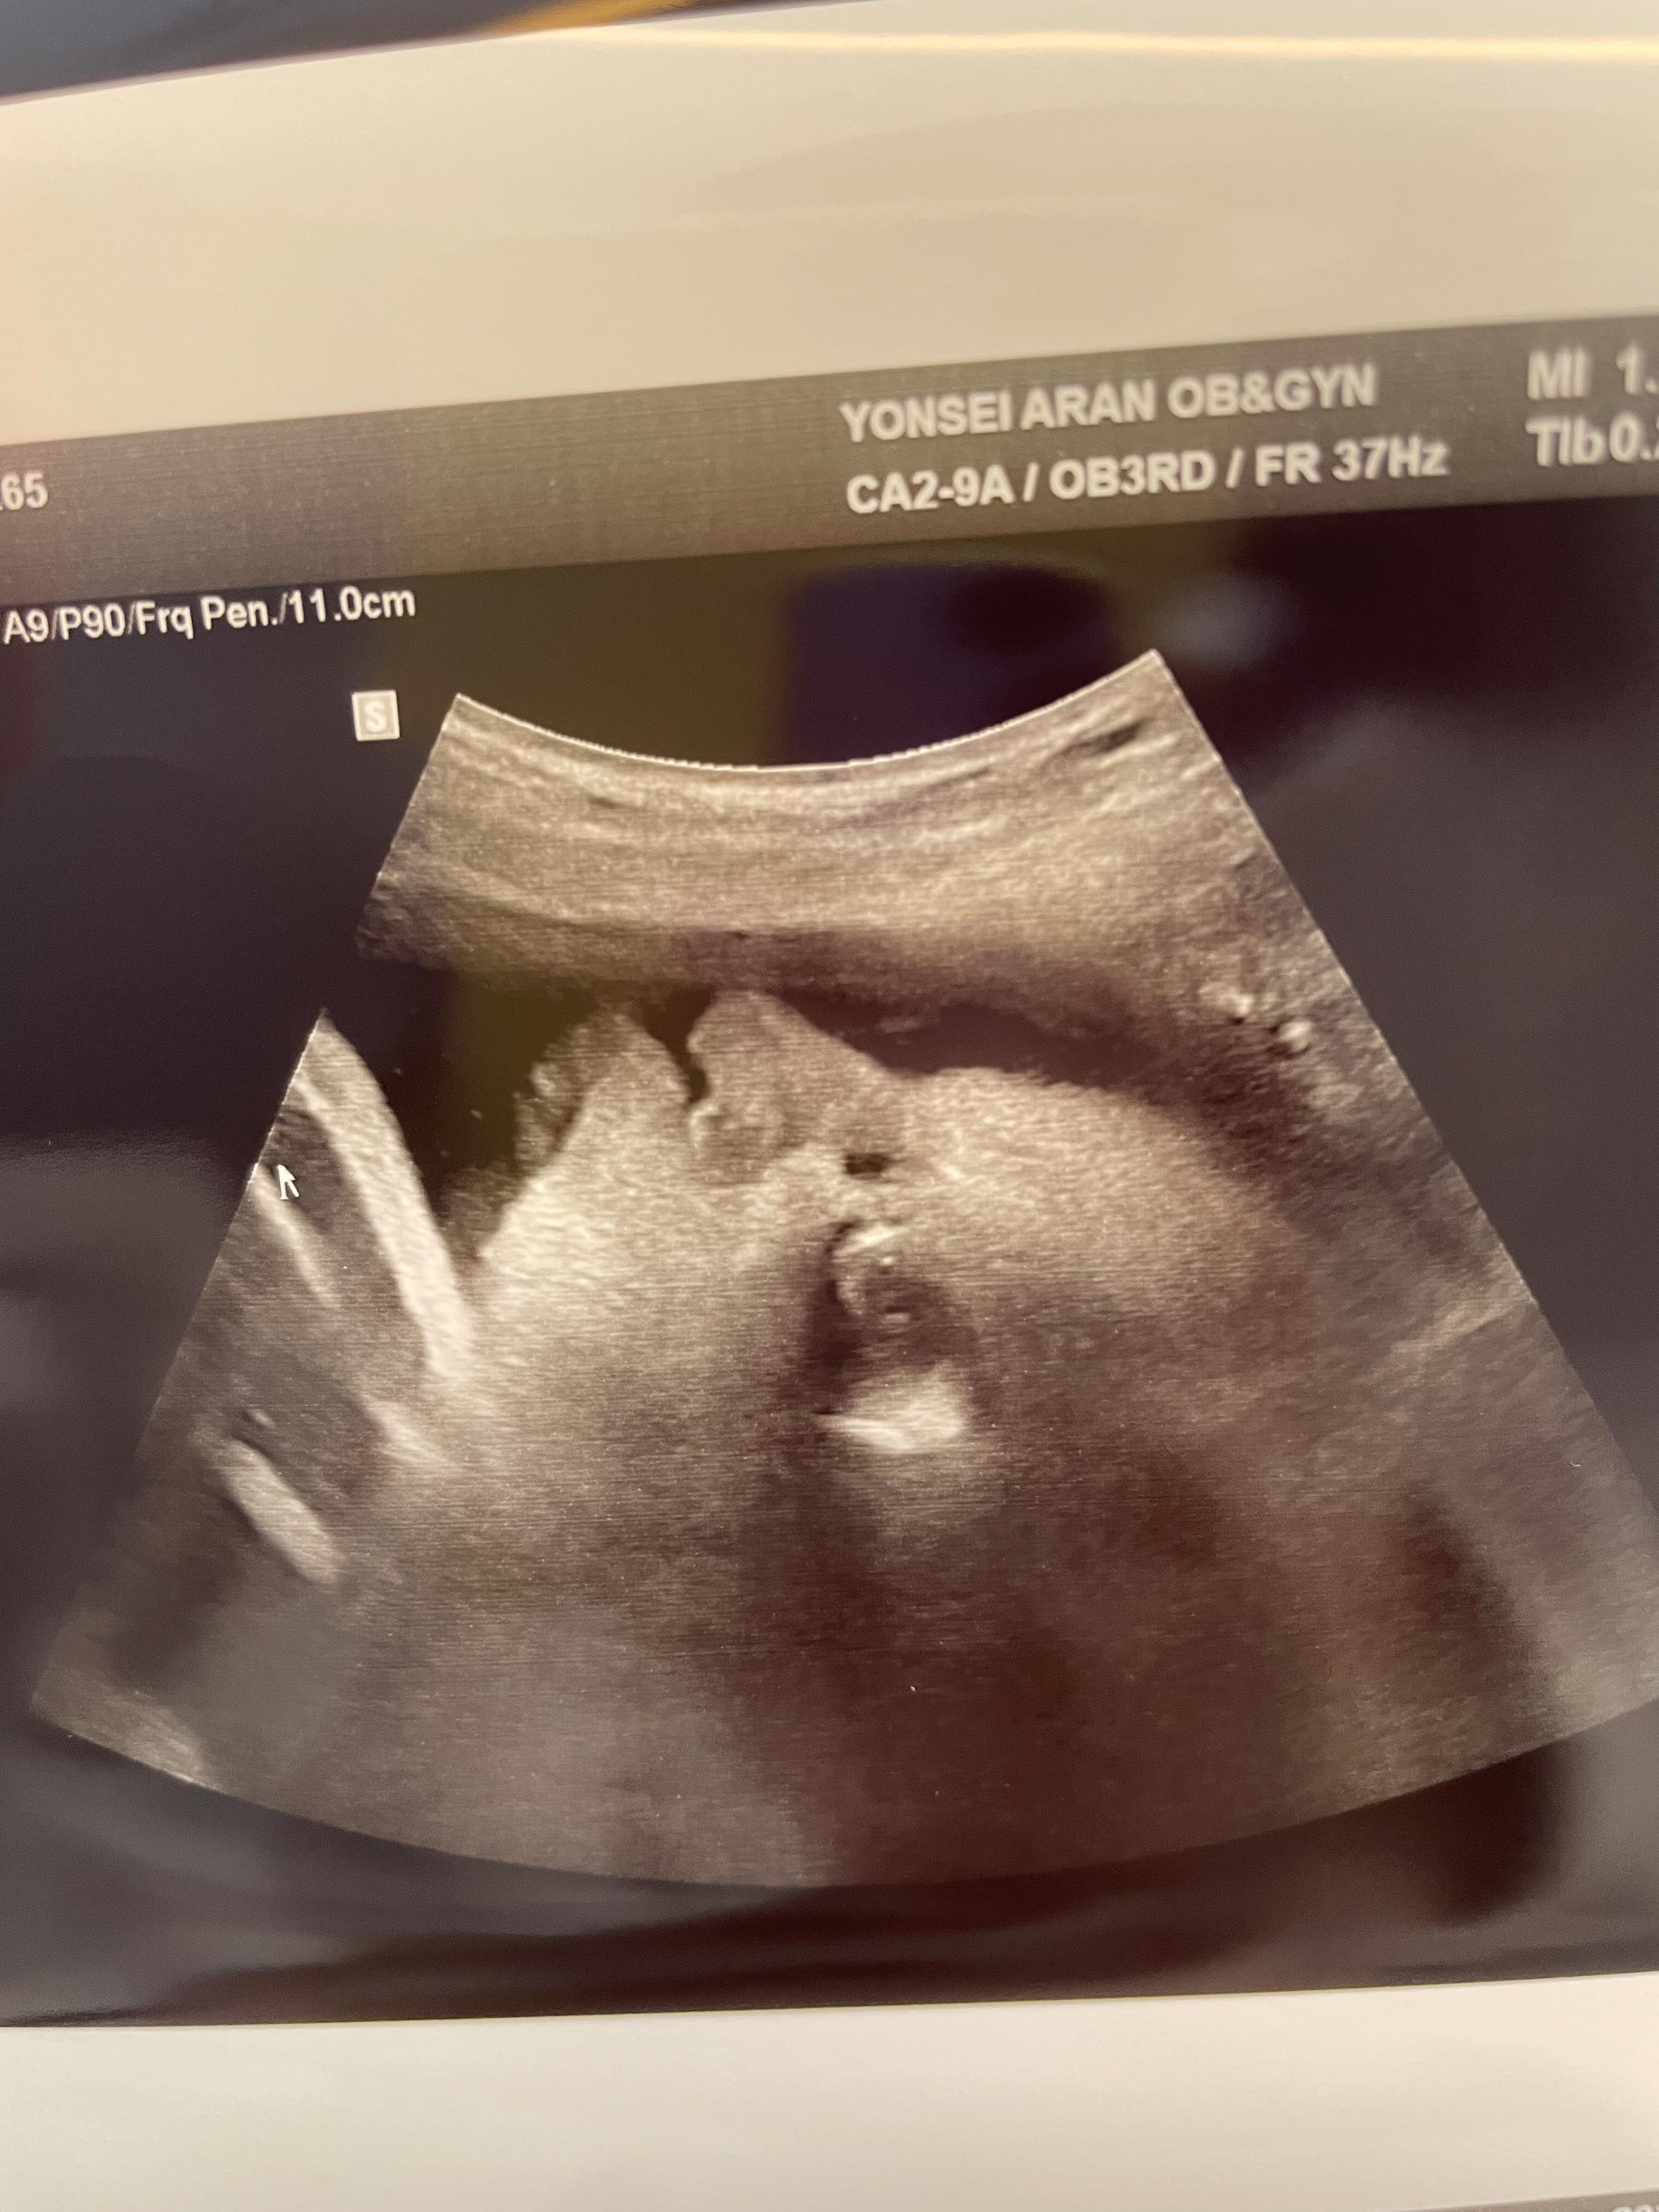

애기가 얼굴이 너무 잘보인다며 웃으셨다.

하나도 안내려왔다고...ㅠ

그와중에 머리는 역시 커졌고,